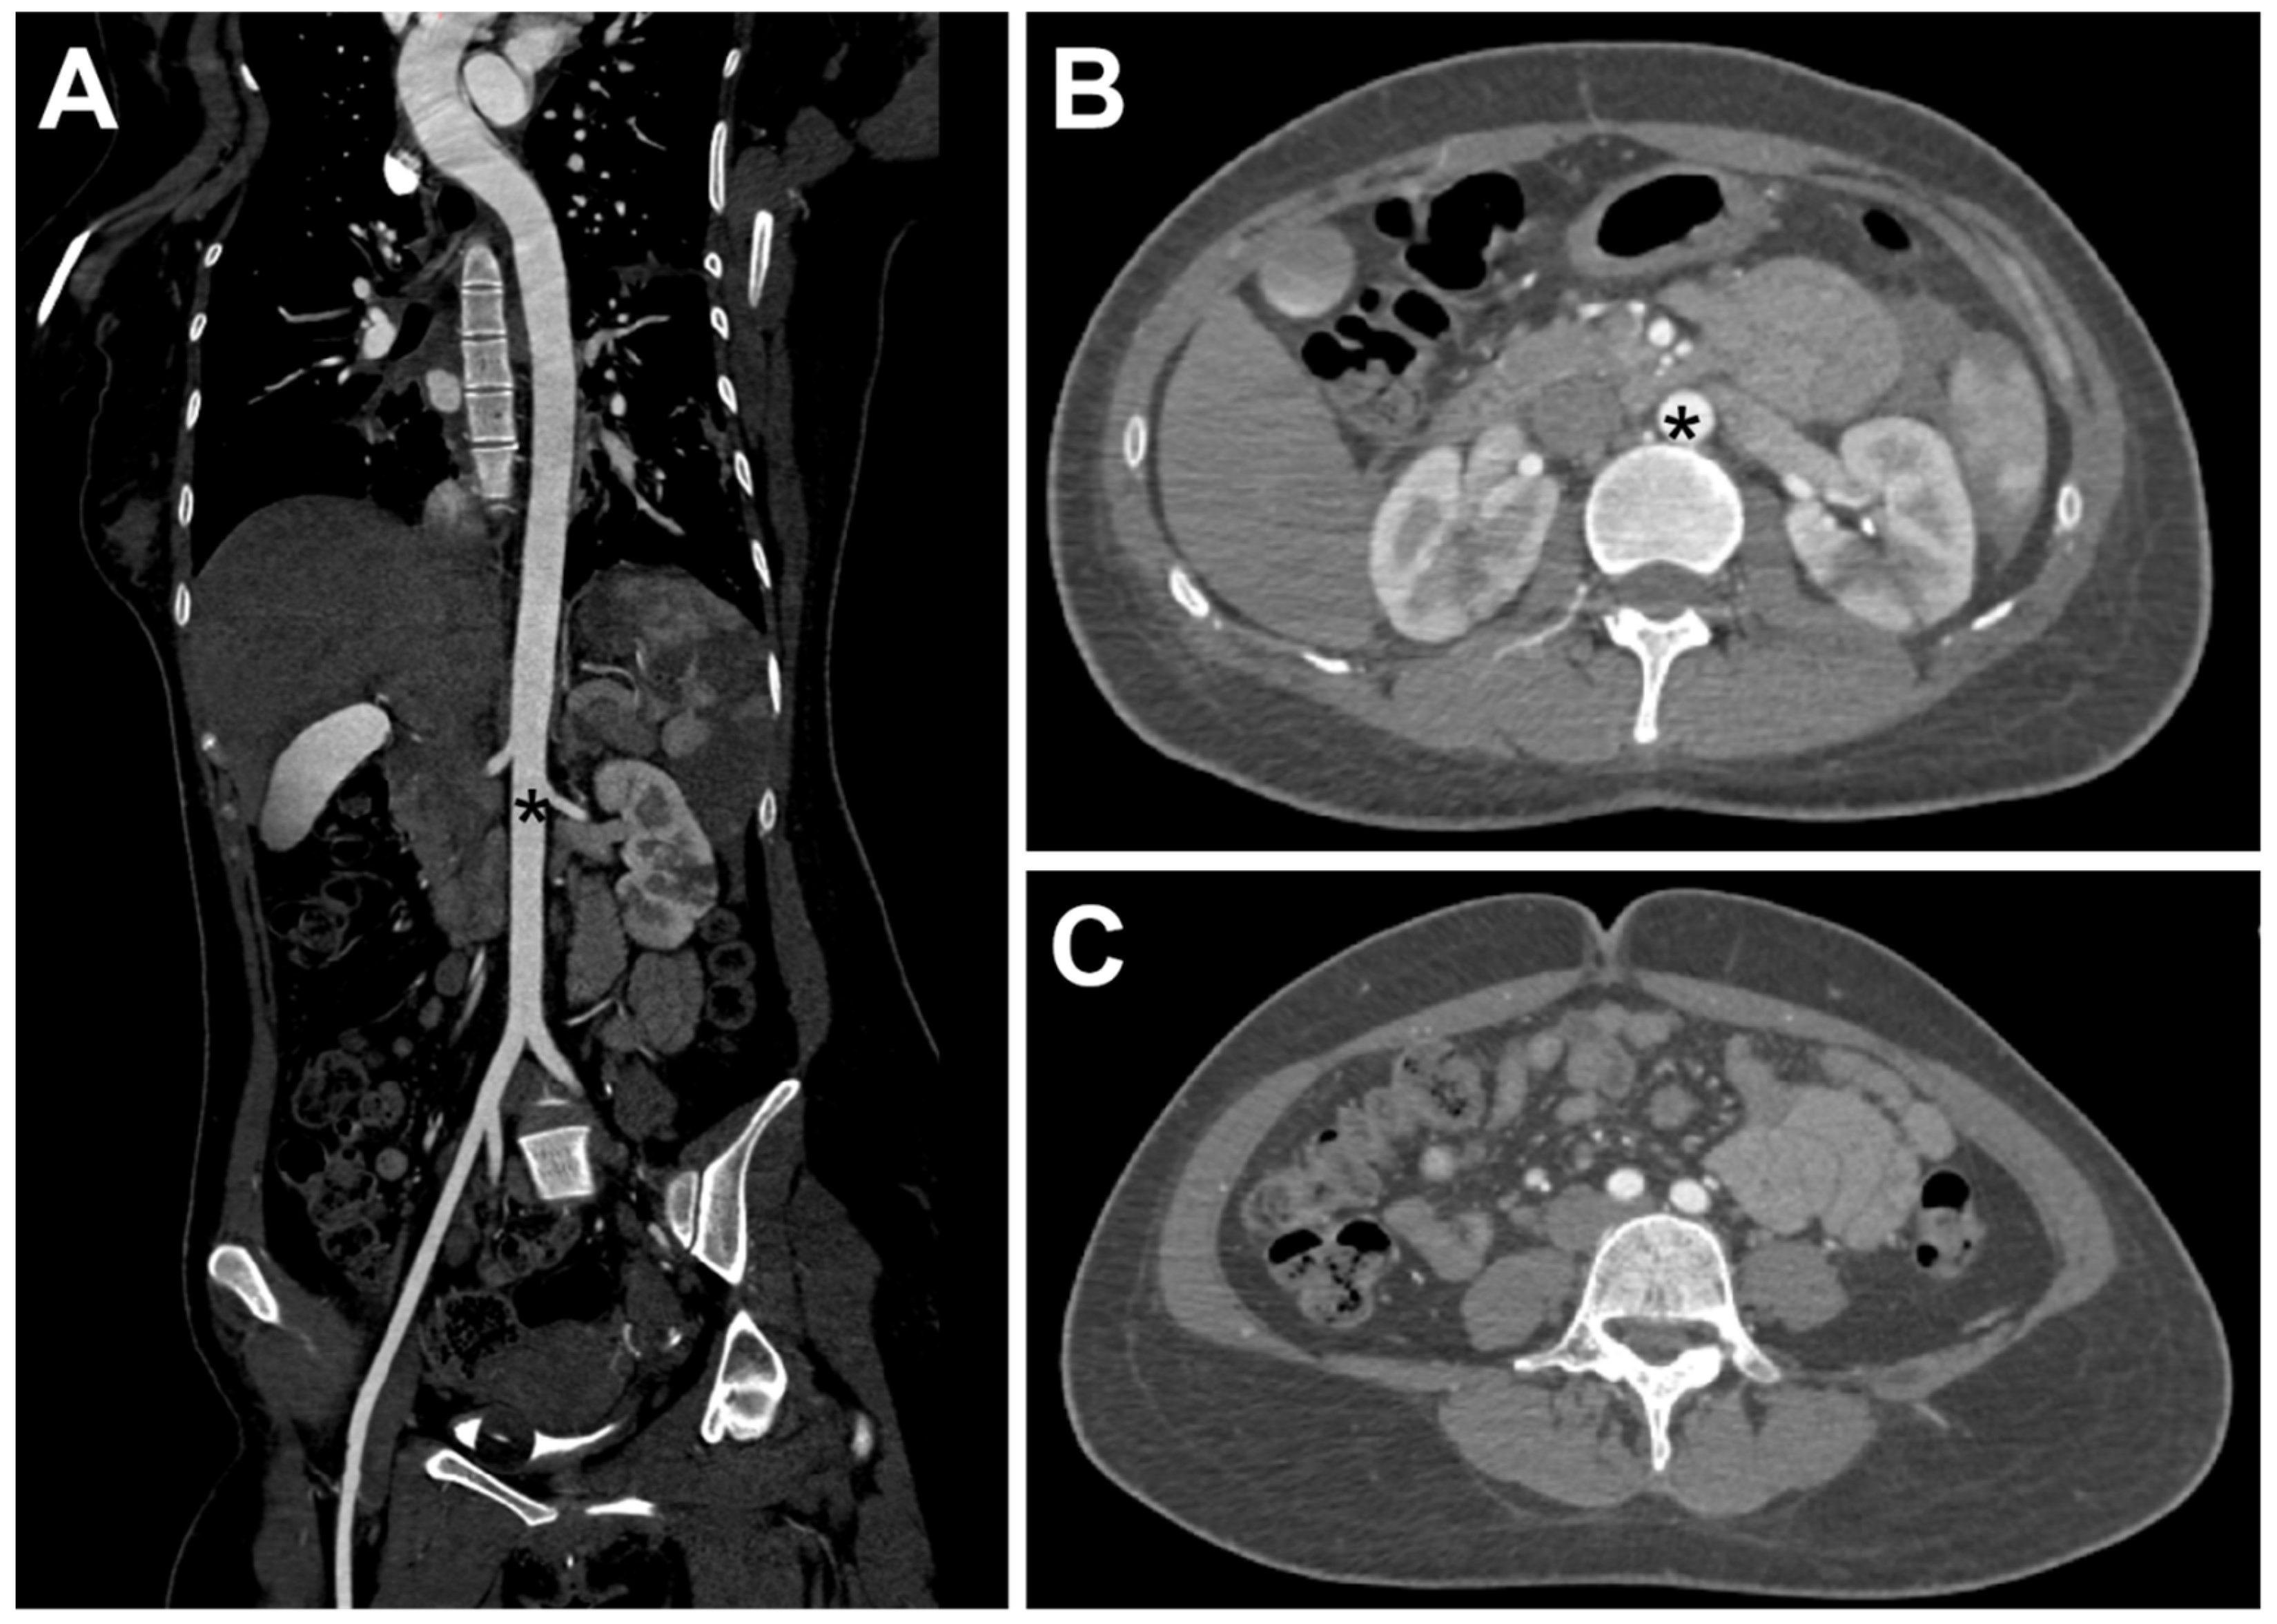

2. Case Report